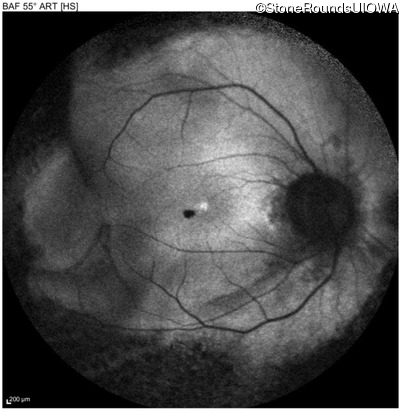

Autosomal Dominant Vitreoretinochoroidopathy (III4A)

Age at visit: 47 years

OD OS

This 47 year old woman began wearing glasses at age 5 and had cataract surgery at age 32. At that time her doctor noticed a retinal abnormality.